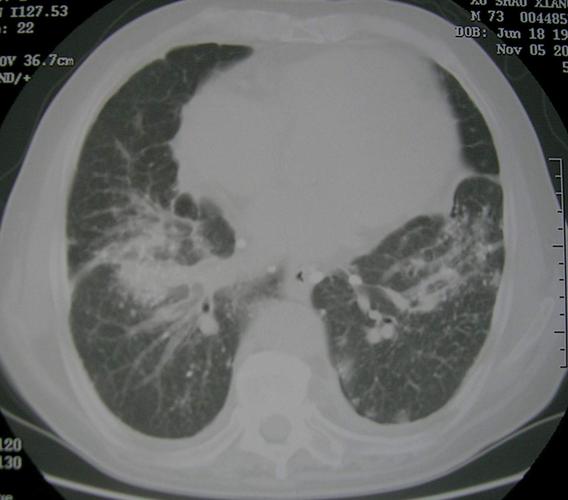

矽肺三期

矽肺三期,矽肺胸片

矽肺3期的影像图片

矽肺CT

矽肺影像图片

矽肺ct图片